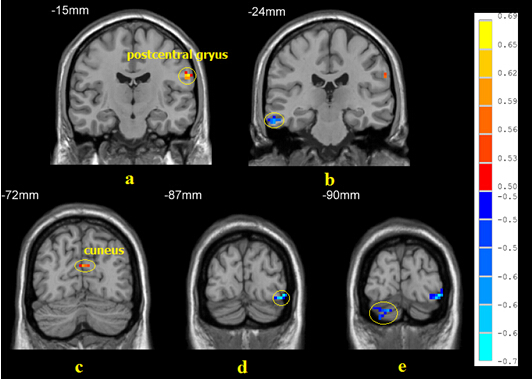

我们针对男性同性恋及男性异性恋者的静息态MRI数据进行了研究,发现:①男性同性恋组在静息态下ReHo显著增高的脑区有左直回、双侧中脑、左颞叶,ReHo显著下降的脑区有左枕下回、右枕中回、右枕上回、左楔叶和右楔前叶(图9)。男性同性恋组中ReHo与金赛量表评分显著正相关的脑区有左枕下回、左小脑、左中央前回、右中央后回,显著负相关的脑区有左运动上回和右顶上回(图10)。②采用低频振幅比例(fALFF)来比较男性同性恋与男性异性恋的静息态脑功能特征,发现:男性同性恋组静息态fALFF较强的脑区有右额中回、右小脑前叶,fALFF较弱的脑区有左中央后回、左舌回、右苍白球、右中央后回、左顶下回、右颞上回、左楔叶、左额下回(图11);左中央后回、左楔叶的fALFF与同性恋性取向呈正相关;而左枕下回、右颞下回、右小脑后叶的fALFF与同性恋性取向呈负相关(图12)。

图12. 男性同性恋组静息状态下低频振幅比率(fALFF)与金赛量表评分相关的脑区(相关分析,p < 0.01, corrected)。暖色和冷色分别表示正相关和负相关。指出的脑区分别为:(A)左中央后回;(B)右颞下回;(C)左楔叶;(D)左枕下回;(E)有小脑后叶。